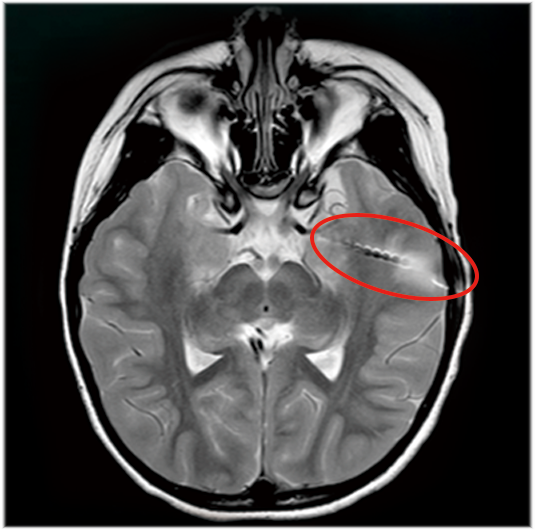

6、满足3.0T核磁兼容要求

临床试验中,瑞神安SEEG验证了3.0T核磁检查的安全性,所有材料均无磁性(电极触点为铂铱合金,导向螺钉为钛合金,导丝为镍钴合金)。

瑞神安SEEG注册临床试验MRI图像